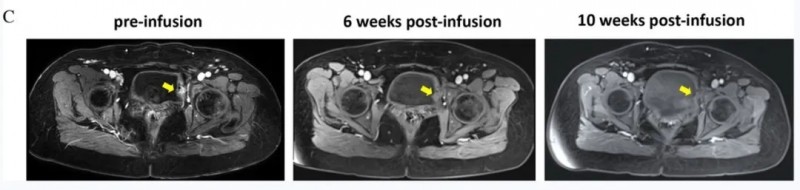

疗效结果显示:TIL输注6周(42天)后,T1WI影像可见病灶显著缩小(黄色箭头),首次临床评估显示患者无发热、体重减轻,体格检查未触及浅表淋巴结肿大;依据RECISTv1.1标准,输注10周后确认达到完全缓解(CR,详见下图)。

▲图源“BMJ journals”,版权归原作者所有,如无意中侵犯了知识产权,请联系我们删除